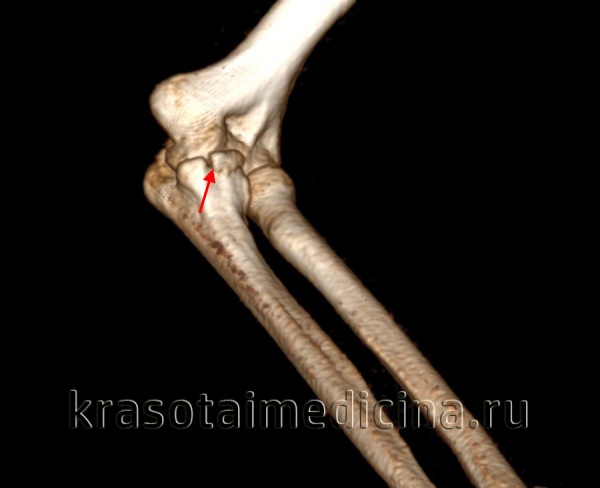

(Справа) На сагиттальной МРТ PDBИ определяется частичный отрыв сухожилия трехглавой мышцы с небольшим оторвавшимся костным отломком МРТ может быть информативна при оценке степени повреждения трехглавой мышцы. (Слева) На сагиттальной КТ с реформатированием можно видеть раздробление локтевого отростка после падения на локтевой сустав. Перелом открывается на суставную поверхность в нескольких местах.

о КТ: сагиттальная с реформатированием для оценки величины щели между суставными поверхностями

(Справа) На осевой КТ виден перелом медиального края локтевою отростка без смещения. Продольные переломы проксимальною конца локтевой кости без смещения иногда очень сложно обнаружить на рентгенограммах. (Слева) На фронтальной МРТ Т1ВИ у этою же пациента видна линия неполною перелома с низким сигналом в локтевом отростке.